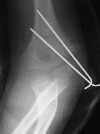

A five year and six month old white male sustained a fall

onto his outstretched right arm with immediate complaints of pain

and swelling in his right elbow. The child was unable to move

his arm secondary to pain. He was on the play ground and the fall

was not witnessed. Physical examination revealed swelling, tenderness

and crepitus over the lateral aspect of the elbow. The skin was

intact and neurovascular examination of the right upper extremity

was without deficits. The patient was taken to the operating room

where under general anesthesia and tourniquet control, the fracture

was exposed utilizing an anterolateral approach. Two diverging

k-wires were placed across the fracture site.